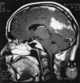

Tuberculosis of meninges

Tuberculous meningitis is also known as TB meningitis or tubercular meningitis. Tuberculous meningitis is Mycobacterium tuberculosis infection of the meninges—the system of membranes which envelop the central nervous system. [Source: Wikipedia ]